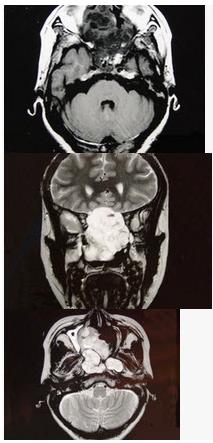

女性,41岁,鼻腔流脓涕3年,鼻部面部肿胀1年,近来加重,MRI检查如图,请选择最可能诊断()

A:鼻腔内囊肿

B:鼻腔内出血

C:鼻腔软骨瘤

D:鼻咽癌

E:鼻腔血管瘤